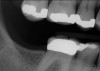

Another consideration is mean vertical displacement of unhampered posterior teeth, which in some studies was minimal: 0.8 mm37 and 0.9 mm30 (Table 1). Yet, there could have been sites where the amount of extrusion was clinically relevant. When Lindskog-Stokland et al assessed the risk of over-eruption using 1 mm as a threshold, they stated there was an odds ratio of 3.3 that unimpeded molars would extrude 1 mm compared to opposed molars.30 Based on their calculations, however, it is unclear which patients with a missing molar are at risk of over-eruption (Figure 1 through Figure 4). Indeed, if susceptible individuals could be identified, then restorative therapy could be initiated to stabilize their occlusion (eg, tooth replacement). Furthermore, odds ratios can be highly misleading, and predictive values would provide clinicians a better perspective as to what percentage of sites may experience significant extrusion.41,42

Fig 1. In 2009 patient No. 1 presented with a missing tooth at site No. 31.

Figure 1

Fig 2. In 2016 patient No. 1 manifested no alterations of tooth position No. 2.

Figure 2

Fig 3. Patient No. 1, contralateral side; in 2009 patient presented with teeth Nos. 15 and 18. Subsequently, tooth No. 18 was extracted due to tooth fracture.

Figure 3

Fig 4. Patient No. 1 in 2016, with extrusion of tooth No. 15. Two different experiences in the same mouth, as shown in Figs 1–2 and Figs 3–4, underscore the unpredictability of extrusion.

Figure 4